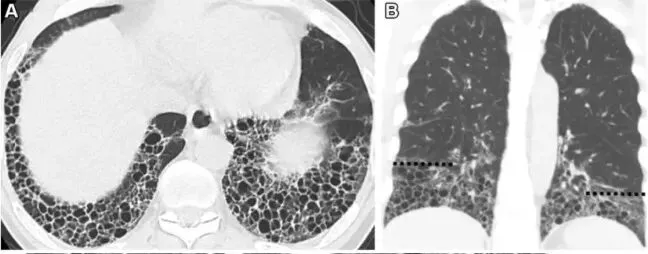

CT表现:成簇的囊状气腔, 直径3~10 mm, 但偶可达2.5cm。蜂窝常位于胸膜下清楚的壁为其特征, 它是一种可确定为肺纤维化的CT征象。蜂窝对诊断肺纤维化特异性, 是诊断寻常性间质性肺炎的重要标准, 但对该术语的应用要慎重,因为它可能直接影响病人的照护。

•  蜂窝肺代表肺实质的破坏,表现为肺结构丧失、边缘清楚和互相比邻的囊状结构,通常簇集状分布于胸膜下区。

• 蜂窝肺传统的定义需要多层囊,但在现今的实践中,只要出现纤维化的其他征象,单层囊便可。

• 囊腔的直径和壁厚度不一,但正常肺结构的完全丧失必然会出现,且常伴随其他肺纤维化征象,如牵拉性细支气管扩张。蜂窝肺也可存在于微观水平而致CT不能发现。

国内的大咖陈启航教授总结的蜂窝肺HRCT特征:

• 蜂窝影直径3-10mm,最大可达数厘米

• 有明确的囊壁,厚约1-3mm

• 囊状影内是气体密度,不是肺实质密度,且不含任何解剖结构(包括小血管、小气道)

• 囊状影呈簇状或多层排列,且互为囊壁

• 分布于胸膜下,并紧贴胸膜面

• 囊状影不呈分支状

• 常伴其它纤维化征象(如牵拉性支扩)